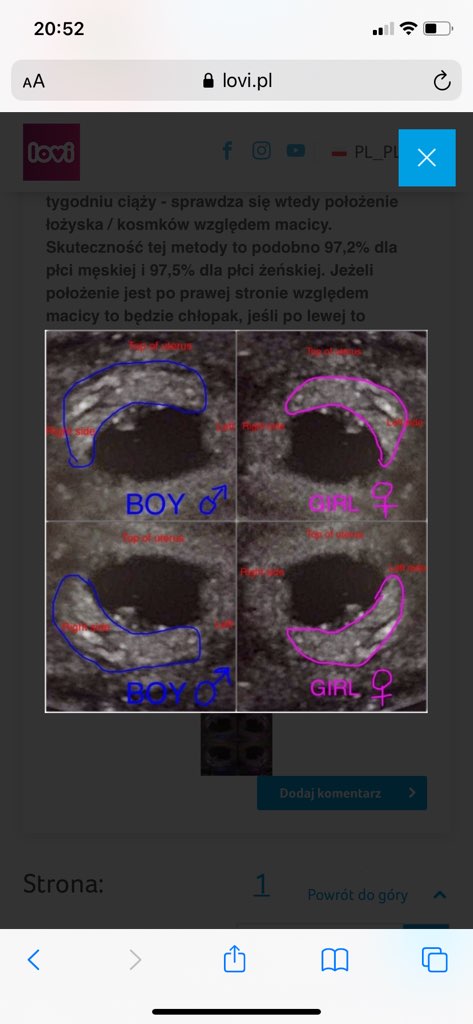

Patrzcie, znalazłam metodę na przewidywanie płci 😂 wiem ze niepotwierdzona itd. ale pobawić się można a akurat się sprawdzi 😅

Z tego wychodzi mi ze jednak chłopak 😅